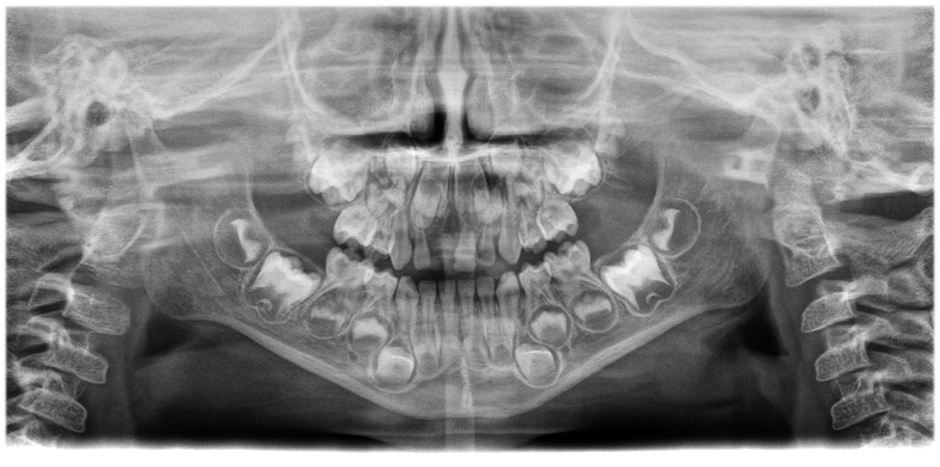

Corrección de posición y movimiento

El avanzado algoritmo de corrección del movimiento lleva la calidad de imagen a un nuevo nivel tanto en imágenes 3D como 2D. Las imágenes 2D mejoran notablemente gracias a un sistema de enfoque automático de 21 capas integrado a la perfección con la corrección de posición.

• Imágenes panorámicas de nitidez y definición extraordinarias

gracias al innovador sistema de enfoque automático de 21 capas integrado a la perfección con la corrección de posición del paciente.

Mueva el botón deslizante para ver la diferencia (a la izquierda, imagen sin enfoque automático; a la derecha, con enfoque automático y posición corregida del paciente).